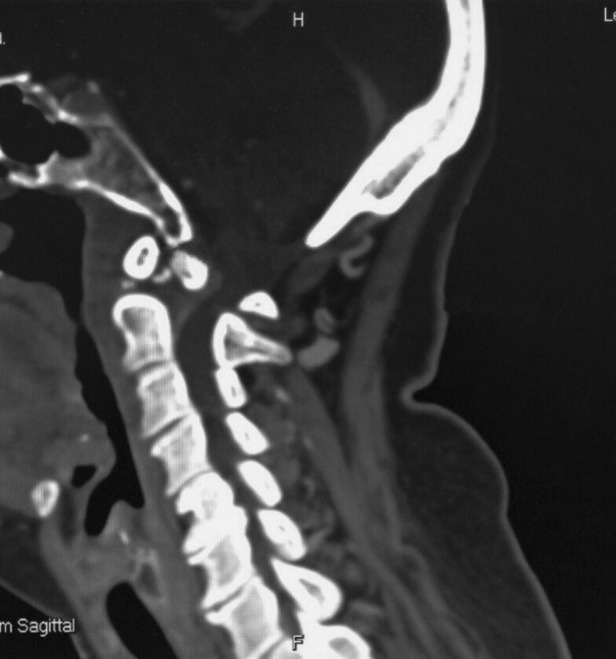

Fig. 3.

Computed tomographic scan of cervical spine in midsagittal view showed dystopic type of os odontoideum and posterior atlantoaxial subluxation. Anterior osteophyte formation of the vertebral bodies with narrowing of intervertebral disc space. The measurement of PADI, the distance from posterior surface of dens to anterior surface of posterior arch of C1, was 12 mm